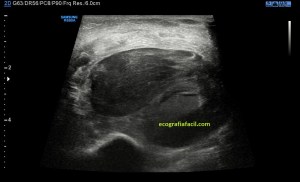

En este breve post te voy a presentar unas imágenes muy bonitas de una vesícula, en una paciente que acude a la cita de ecografía por sospecha de patología a ese nivel, con molestias anodinas e inespecíficas en el contexto de un estudio de su especialista de digestivo.

Observa las imágenes y luego te explico los hallazgos:

Cuando hice el corte longitudinal de la vesícula pude ver hasta tres patologías distintas, una adeomiomatosis (sin artefacto en cola de cometa), una litiasis vesicular y barro biliar, 2,3 y 4 respectivamente.

El caso no tiene mucho que explicar a no ser por la rareza de que se presente triple la semiología patológica en una misma imagen.

La adenomiomatosis, como un aumento de la ecogenicidad y el tamaño de la pared vesicular, la litiasis como una estructura hiperecogénica con sombra acústica posterior y el barro biliar, hiperecogénico rellenando toda la estructura ovoidea de la vesícula.

El cuello vesicular estaría afectado por la adenomiomatosis, el cuerpo por la litiasis y el barro ocuparía el fundas vesicular.

Para el estudio de la adenomiomatosis es obligado que el foco esté situado en la línea de interés, eso hará que las imágenes sean más nítidas y podamos estudiar dicha ecoarquitectura y su patología convenientemente.

Debemos observar si existiese líquido perivesicular, o signos de colecistitis. En este caso, la paciente, con estas tres patologías ya iba bien servida.